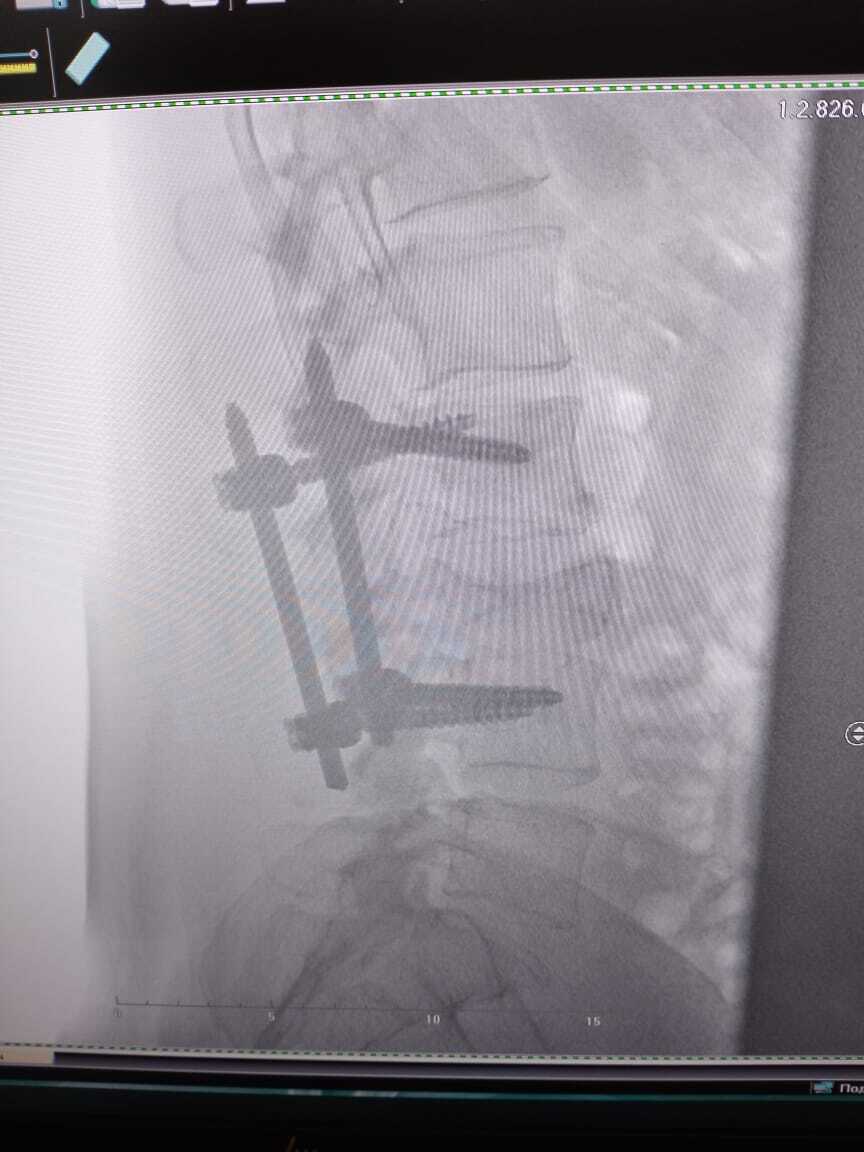

По позвоночнику, так как один болт решил сместится то ортопед ( лечащий)советует переделать конструкцию ( расширить на другие позвонки , чтобы распределить нагрузку как я понял) или поставить типо протеза" диск " . Операция на переделку по квоте - очереди 3 месяца+, на протез " диск" - пол года +. Или на платной основе, переделка 200+-, протез 400+-. Но другой ортопед , из онко больницы в Москве, советовал не лезть туда - потому что сломанный позвонок закостенел уже , но если болты " двигаться " будут то будет больно. Теперь я в раздумьях, с одной лучше сделать и не будет ограничений физических- но опять восстанавливаться долго. А с другой стороны опять операция , не будет ли по онкологии осложнений потом. Вы как думаете? Сейчас из за позвоночника ограничения - тяжёлое не поднимать, и сидеть долго не могу. Часто с палкой хожу, но это еще из за ноги...